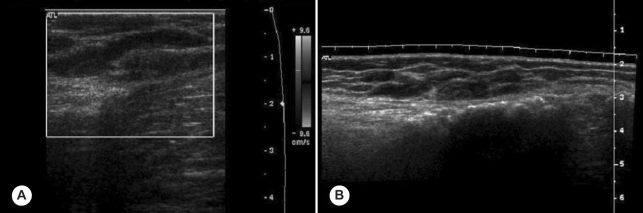

On physical examination, relatively ill defined, variously sized, round or elongated, soft nodules were detected on the medial aspect of her left leg and popliteal fossa. Routine laboratory test results were within reference ranges, and no leukocytosis and no eosinophilia was detected in the peripheral blood. A plain knee radiograph taken at a primary clinic demonstrated multiple discoid calcifications around her knee (Fig. 1). Ultrasonography revealed subcutaneous hypoechoic elongated nodules and irregular intramuscular calcifications in the left lower leg antero-medially with slightly increased peripheral vascularity. Elongated and dilated superficial veins were also identified along the hypoechoic nodule and this showed compressibility at the same time (Fig. 2). Magnetic resonance (MR) imaging revealed a multilocular (tubular and round) subcutaneous lesion (width 45 mm, thickness 15 mm, length 75 mm) in the antero-medial aspect of the proximal left lower leg. The lesion showed low signal intensity on T1 weighted images, high and low signal intensities on T2 weighted images, and irregular thick rim enhancement. Numerous calcific foci were noted along the medial margin of the soleus and medial head of the gastrocnemius muscle. Sporadic intra- and intermuscular calcific foci were also noted at the postero-lateral portion of the distal thigh, which showed faint rim enhancement (Fig. 3). The preoperative diagnosis was made as a partly thrombosed varicose vein associated with myositis at adjacent muscles.

On plain radiographs, calcification has been reported as an important diagnostic clue of cerebral sparganosis (Chang et al., 1992; Dunn and Palmer, 1998). The sonographic findings include a linear echogenicity with a 'dot and dash' pattern in some portion of the tract, which is a highly characteristic finding of sparganosis (Cho et al., 2002). Our patient also disclosed similar findings, but dilated veins along and around mass with compressibility on ultrasonography made us confusing the diagnosis. The live sparganum, with an overlying soft capsule, was misinterpreted as a partly thrombosed varicose vein. MR images of muscular sparganosis are conglomerated cystic lesions and reactive changes in the adjacent soft tissues. The imaging appearance of the cystic lesions with surrounding reactive changes may resemble pyogenic infections, other parasitic infections (cysticercosis and paragonimiasis) or hemangioma, and these must be differentiated. Moreover, if serpiginous tubular tracts are observed during imaging studies, musculoskeletal sparganosis should be included in the differential diagnosis (Cho et al., 2002). Laminated calcospherules in the cytoplasm of proliferating macrophages and giant cells are of diagnostic value if no sparganum worm is present in a lesion (Chi, 1980).